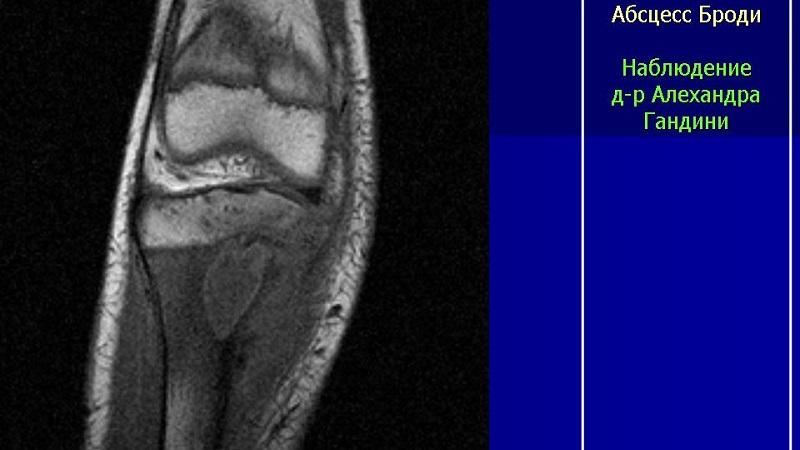

Отличительной чертой абсцесса Броди является наличие четкой изолированной полости без секвестра (участка омертвевшей ткани), имеющей правильную округлую форму. Это состояние можно диагностировать с помощью рентгенологического исследования.

Рентгенография и магнитно-резонансная томография – это единственные методы диагностики, которые позволяют полностью увидеть картину заболевания.

Окончательный диагноз устанавливается на основе четких данных рентгенографии.